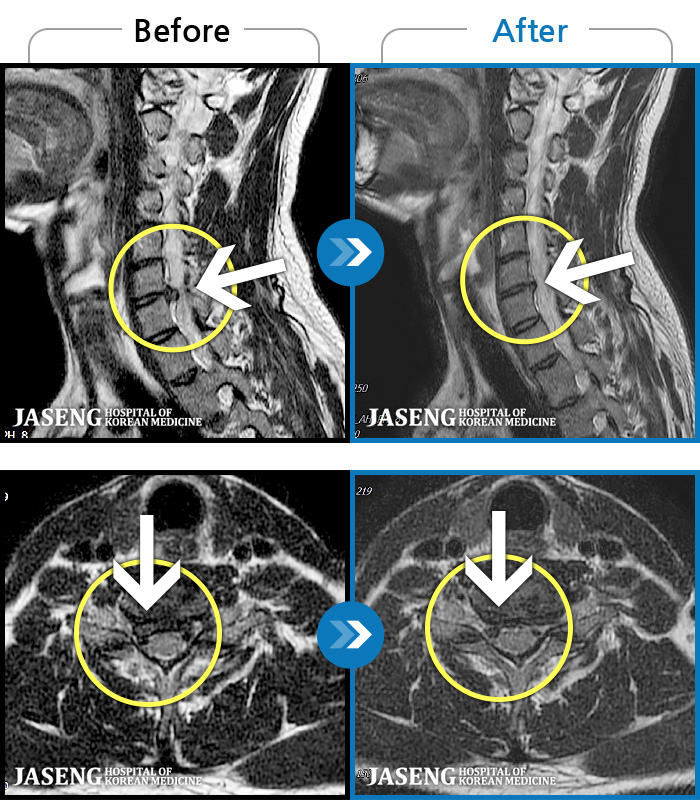

[뱸] 19.11.28~25.05.06

ȯںп Ǹ ǿ ԿǾ, ο ġ ۿ Ƿ ġḦ Ͻñ ٶϴ.